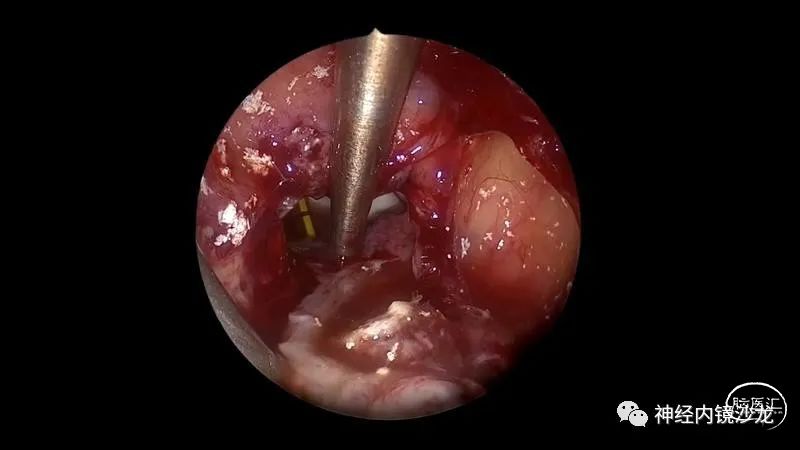

精彩图表

从事神经外科十余年,擅长神经外科肿瘤诊治,尤其是神经内镜微创手术治疗垂体瘤、颅咽管瘤、脑膜瘤等颅底肿瘤